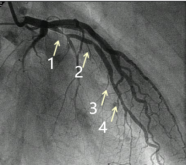

6月15日,81岁冠心病患者陈某(化名)因胸闷、胸痛等不适入院。入院后完善相关检查,行冠脉造影:左主干无狭窄,前降支弥漫性斑块浸润,近段原支架通畅,支架内30%狭窄,支架远段60%狭窄,中远段70%狭窄,回旋支斑块浸润,近狭窄30%,右冠脉弥漫性斑块浸润,开口处70%狭窄,近段60%狭窄,第二后降支次全闭塞。

在心血管内科介入团队的紧密配合下,FFR检测仪器有条不紊地记录下患者血管内的血流情况。经过精准的数据测量,对前降支中段及中远段狭窄进行血流储备分数测定,测得数值0.84,对右冠脉近段及开口处狭窄进行血流储备分数测定,测得数值0.96-1.0,患者冠状动脉狭窄处血流储备分数测得值均大于0.80,综合患者病情及FFR结果,无需植入支架,药物保守治疗即可。